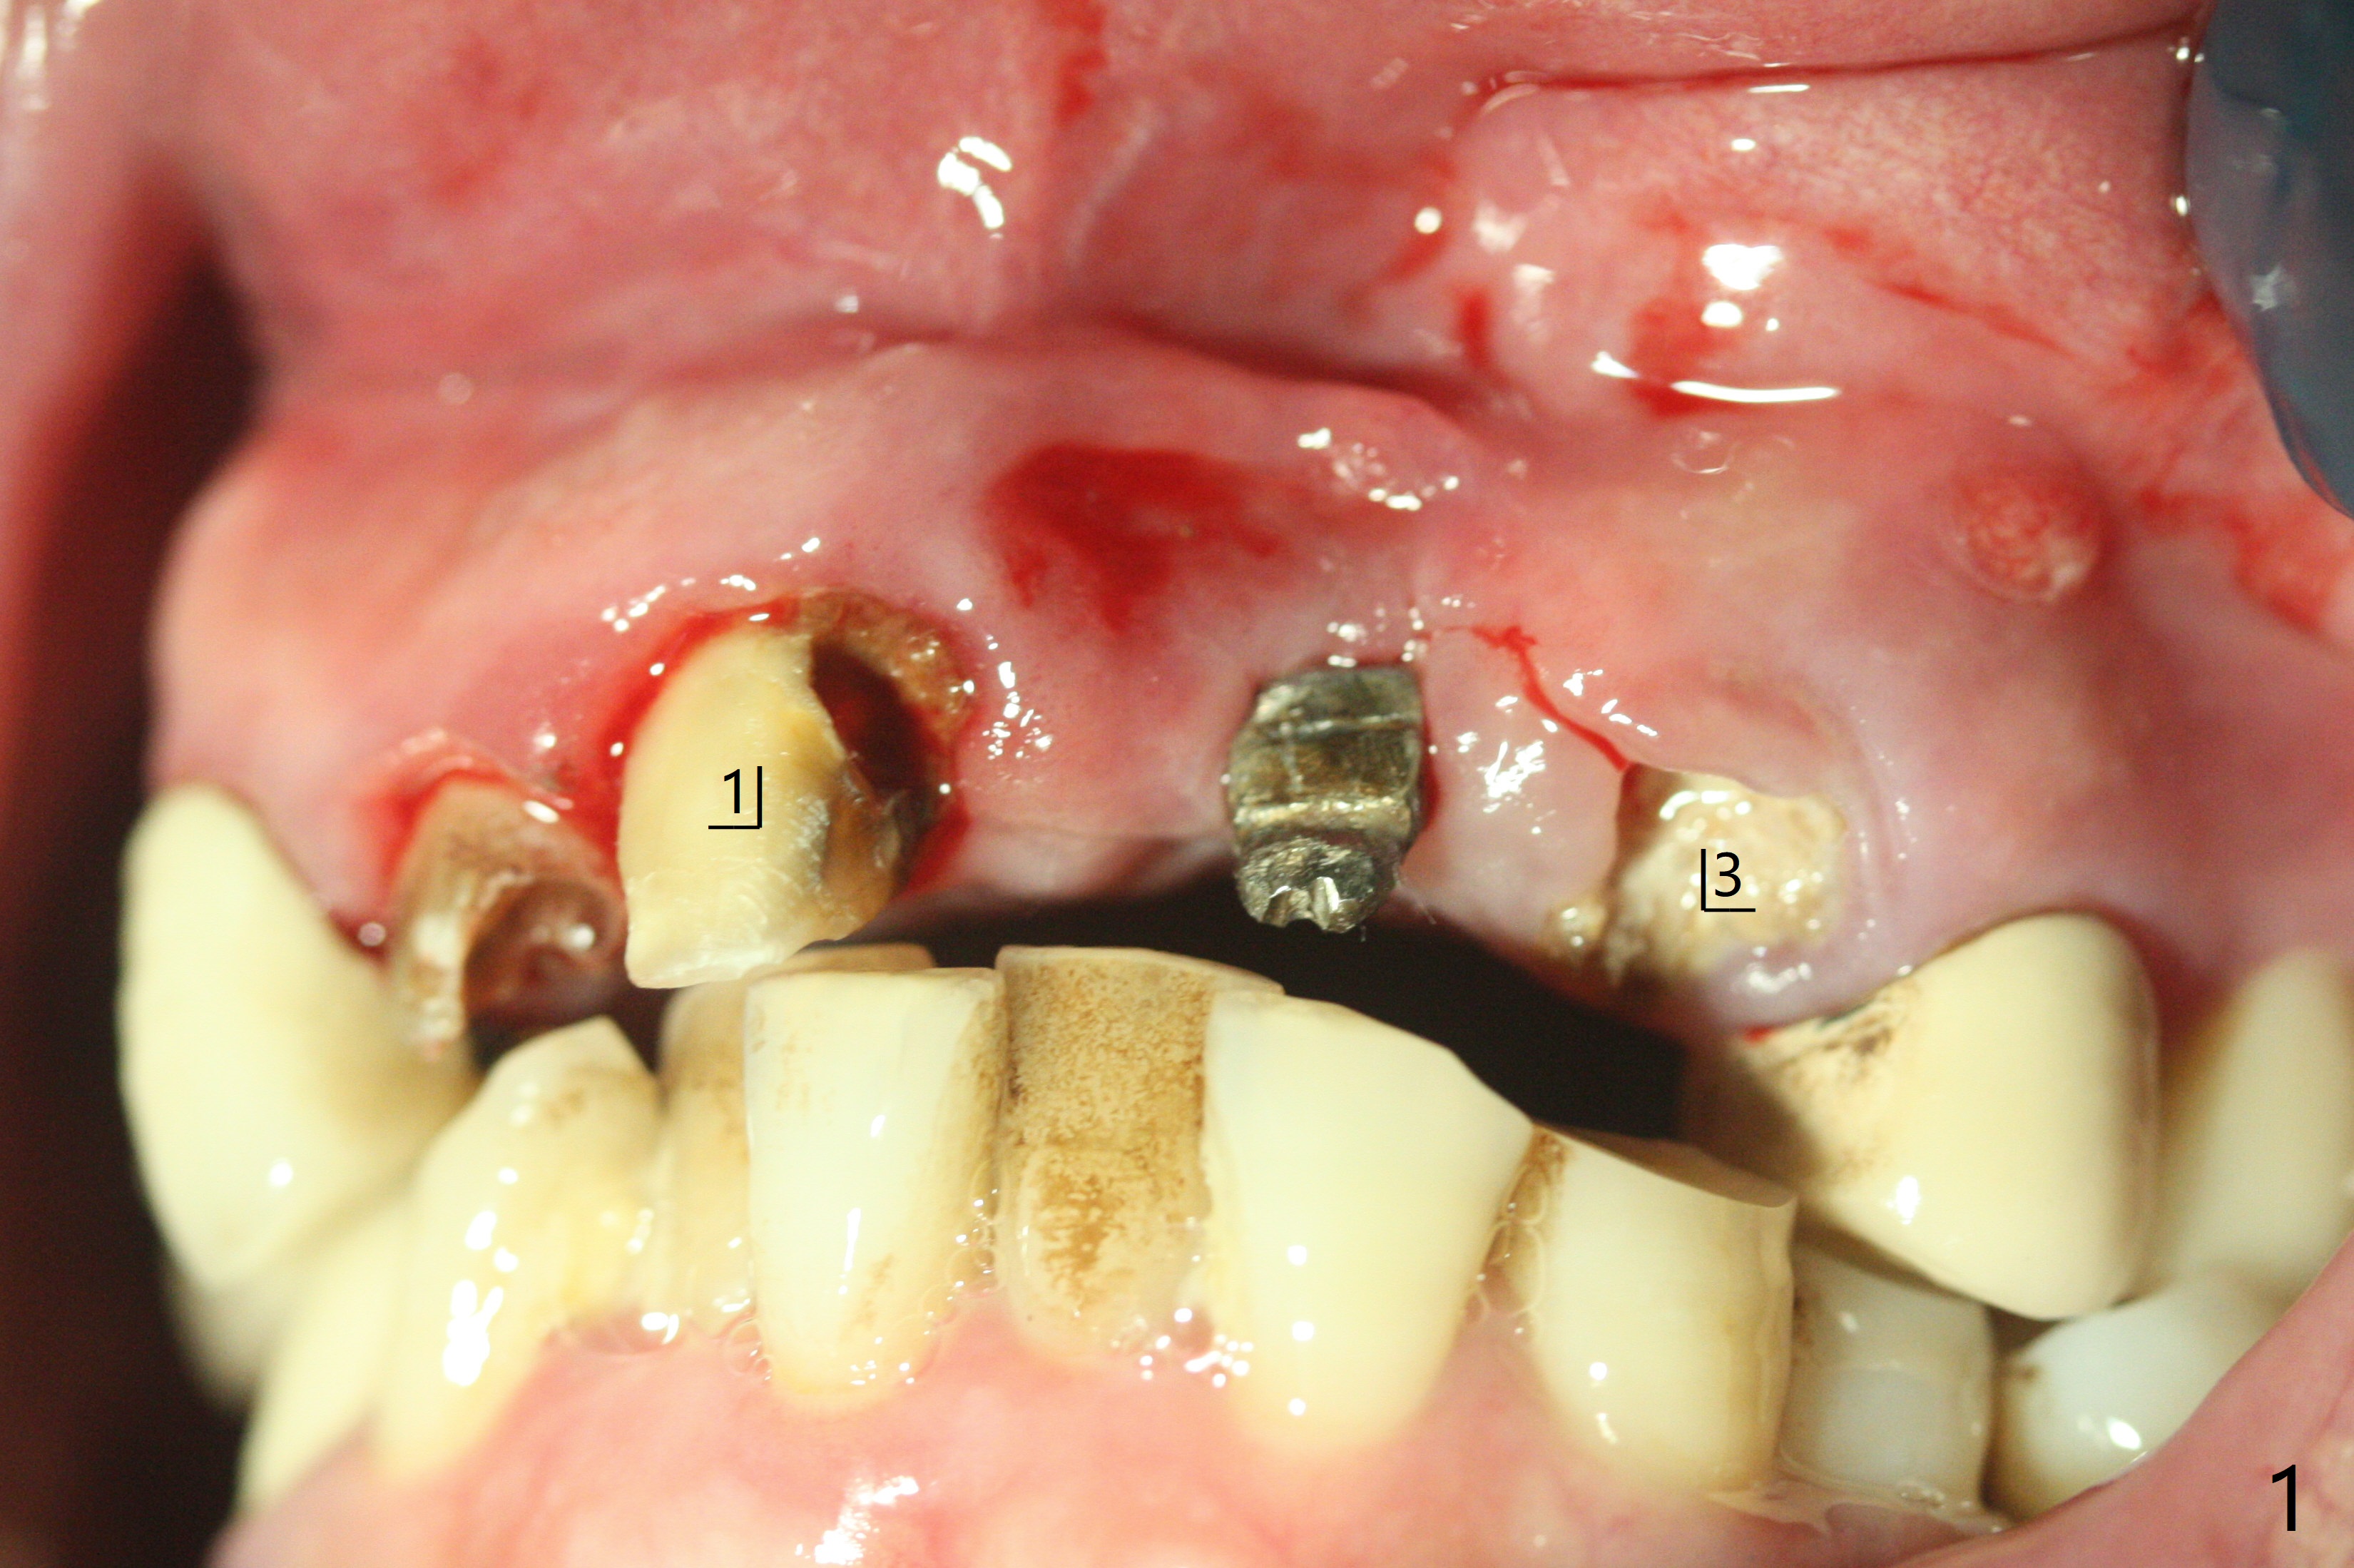

上前牙桥撤除显示右上1,2牙齿以及左上2叶片状植体好像可以保留,而左上3牙齿不能(图一,二(<:托牙边缘压迹)),拔除左上3牙齿后, 暂时把牙桥回位(图三:FPD(已经去除左上3号牙牙冠))作为3号牙种植位置参考(图四至六(G:骨粉))。其实植入前,当最后一个钻头还在原位,将PRF膜和粘性骨放置颊侧根尖(但愿骨粉能放深点),因为那里骨质很薄,好像缺损。由于植体扭力很低(大约5Ncm),放置骨粉覆盖植体(图七),为了不用缝线,涂牙周胶水(图八),放置胶原膜(图九),再涂胶水(图十)固定,最后利用右上1,2号牙(去龋,build-up后)和左上2植体制作临时牙桥,并且覆盖左上3牙槽窝。术后即刻CT显示植体颊侧(B)骨粉(图十一:*)。<:植体根尖仍有间隙,植体应该再长2毫米,初步稳定性会好些。左上3植牙愈合后,将与左上2植体制作左上1-3悬臂桥,右上1,2号牙将做根管治疗,桩,牙冠。临时牙桥术后十一天松动,右上一,二牙牙髓活性测定正常,深洗后,再次build up,不小心把左上3胶原膜吹掉,下面骨粉还稳定。术后三周病人回来做右上六种植,前牙临时修复体(图十二)需要修改(图十三)。拍摄三个方向照片显示前牙牙龈乳头(颊侧和咬合面)。